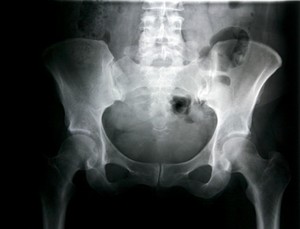

Permainan lain yang patut diwaspadai adalah memanjat pohon. dr Irfan menjelaskan bila si anak suka memanjat pohon dan sering terjatuh dari ketinggian, maka area selangkangannya dipastikan akan mengalami cedera. Bahkan bukan tidak mungkin akan mempengaruhi bagian tubuhnya yang lain seperti panggul.